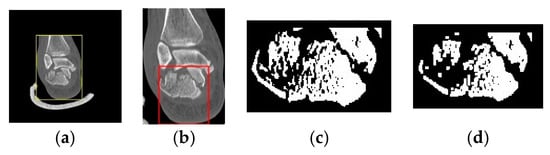

2.4. Step 1: Detection of Calcaneus Location

2.5. Step 2: Segmentation of the Calcaneus Fragments